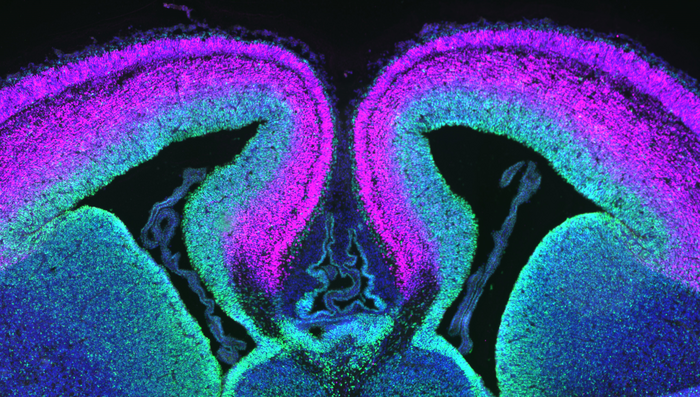

图片:小鼠大脑皮层横切面,绿色标记祖细胞,洋红色标记神经元。杜克大学的研究人员已经确定了一种名为DDX3X的基因在健康神经元形成中的作用。

图片来源:杜克大学黛布拉·西尔弗实验室